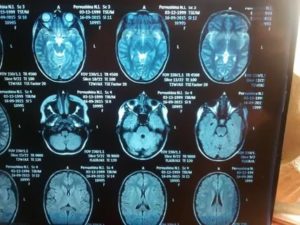

- Магнитный резонансный томограф передает на специальный компьютер результаты обследования. Они отображаются в виде снимков головного мозга. В идеале должно быть 4 проекции: передняя, верхняя, левая и правая.

МРТ головы помогает получить снимки, на которых ткани обозначены затемнениями и просветлениями. Ткани мозга имеют серый цвет. Протекающие церебральные жидкости отображаются в виде ручейков светло-серого оттенка. Черные полости на изображении — это внутримозговые синусы.

Если все области головного мозга развиты правильно, то интенсивность сигнала, полученного от томографа, будет одинаковой. У здорового человека желудочковая система должна иметь нормальные размеры.

Любое ее расширение или уменьшение считается отклонением. В норме должно быть и периваскулярное, и субарахноидальное пространство. Обращают внимание на состояние борозд и извилин.

В них не должно быть никаких отклонений.

Структура самого мозга также должна находиться в пределах нормы. Он не должен быть смещен. Нормальный размер должны иметь глазницы, слуховые проходы и носовые пазухи. В мозговых тканях не должно наблюдаться никаких диффузных или очаговых изменений.